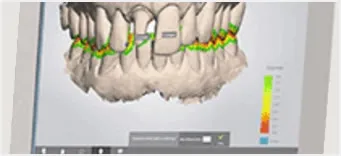

Digital Impressions

Ciudadela Dental Implants has the Highest State of the Art Facility for Dental Implants in Puerto Rico